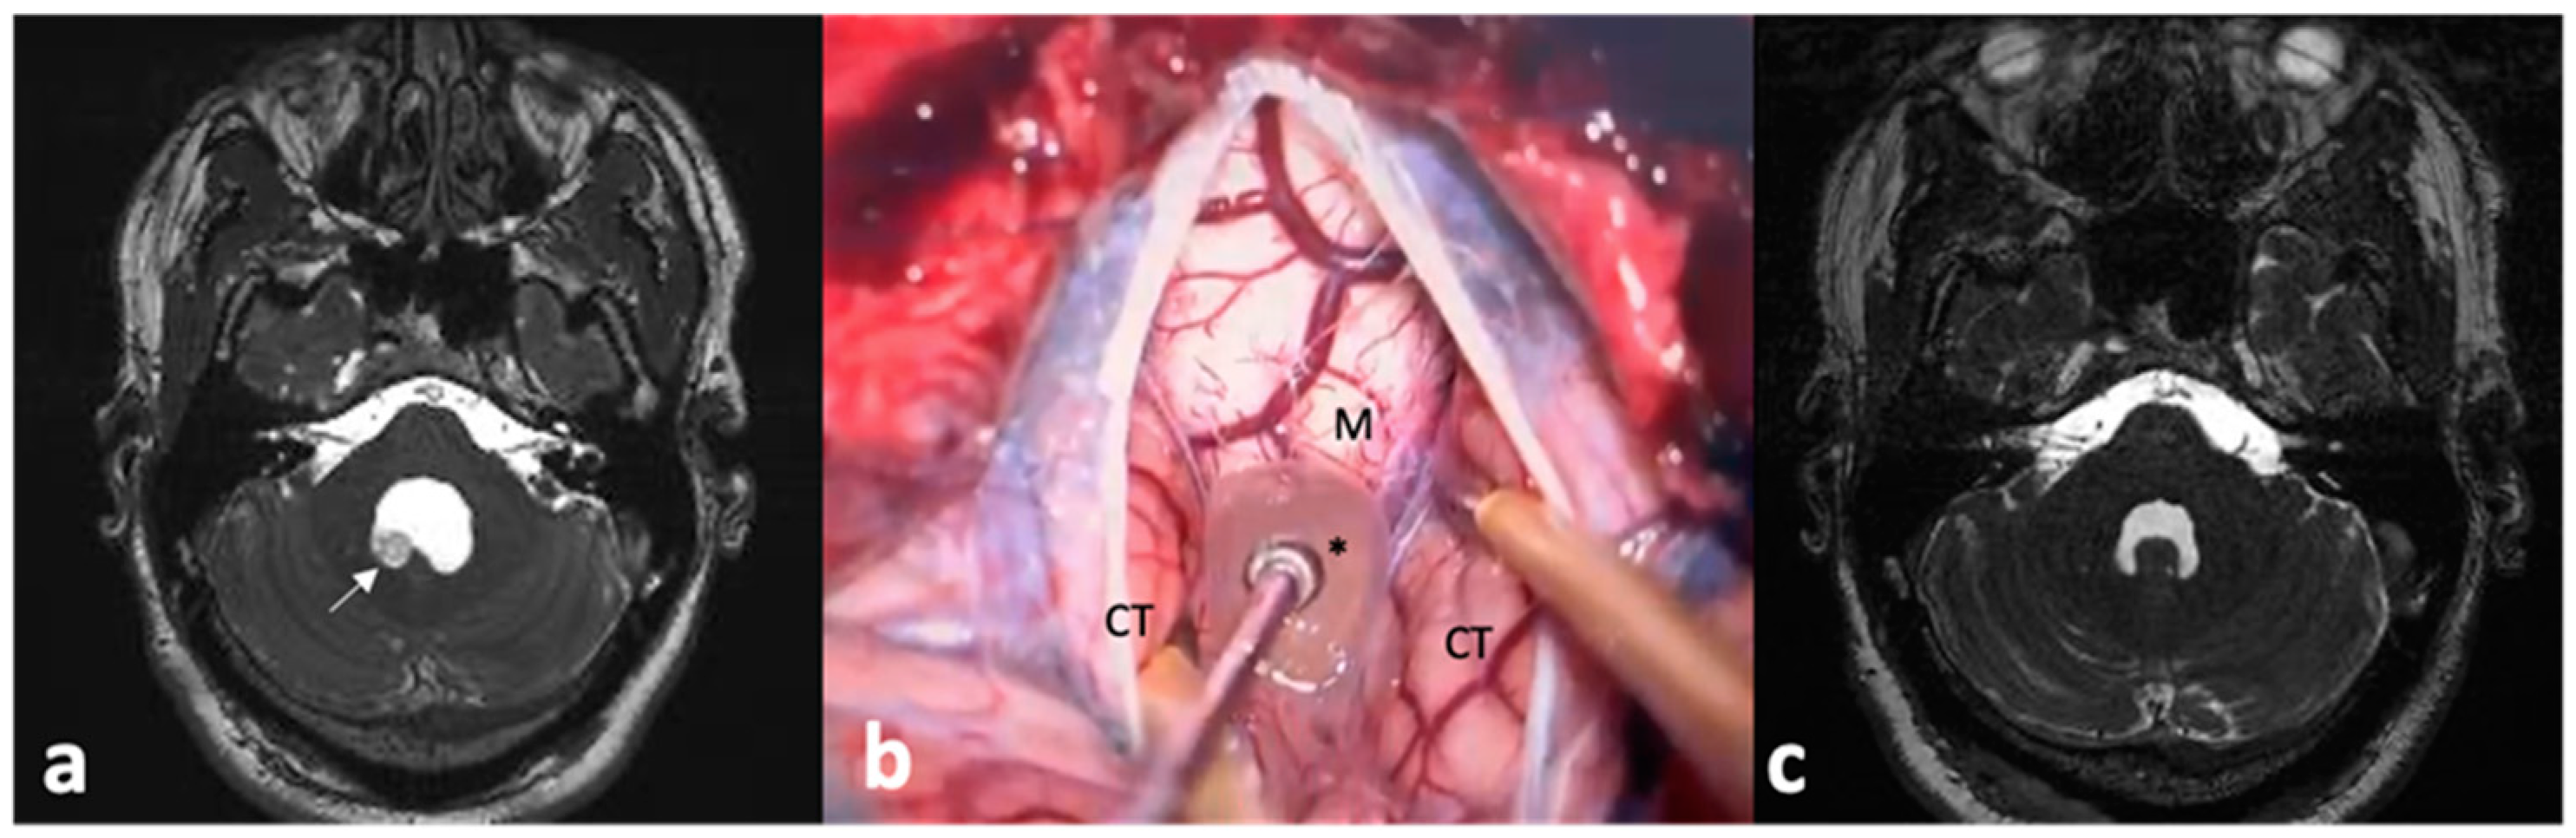

- Lines-Aguilar, W.W.; García, H.H.; Medina, J.E.; Saavedra, L.J.; Vela, E.; Lozano, M.; Vargas, J.; Cuya, C.; Heredia, D.; Apaza-Tintaya, A.; et al. Multimodal Minimally Invasive Surgery in the Treatment of Neurocysticercosis. Interdiscip. Neurosurg. Adv. Tech. Case Manag. 2024, 36, 101872. [Google Scholar] [CrossRef]